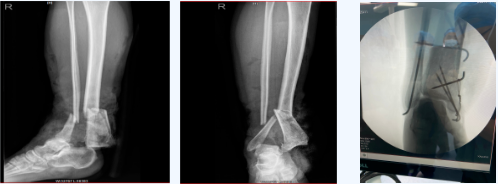

患者刘某因交通事故导致小腿不全离断,被120送来我院后,经手足显微外科会诊与查体:患者血压较低、心率较快、处于休克前代偿期。右小腿中下段开放粉碎性骨折血管长段缺损,大面积皮肤软组织缺损,小腿外侧存在少量皮肤,右足苍白无血运。

患者是一位26岁的年轻妈妈,有三个孩子,最小孩子1周岁,右足能否保住对她来说可能会是两个不同的人生状态。经科室严谨细致讨论后,临床经验丰富的赵建武主任决定为患者取对侧股前外侧游离皮瓣,运用flow-through技术保肢。经过10个多小时手术,该手术采用游离皮瓣flow-through技术并成功实施在多学科的通力配合下,患者右脚恢复了血运,创面也得到了覆盖。术后转入重症医学科进一步治疗,目前患者病情稳定,患足及皮瓣成活,已转手足显微外科病区进一步治疗。

赵建武主任讲:该手术的难度在于游离股前外侧皮瓣及6个吻合口进行吻合,而且血管口径相差悬殊,对术者技术要求非常高,且耗时长,需要有足够的耐心。此手术方式在我院尚属首例,标志着我院显微外科技术有了进一步的提升,为我市周边大肢体离断患者救治提供了新的方法。